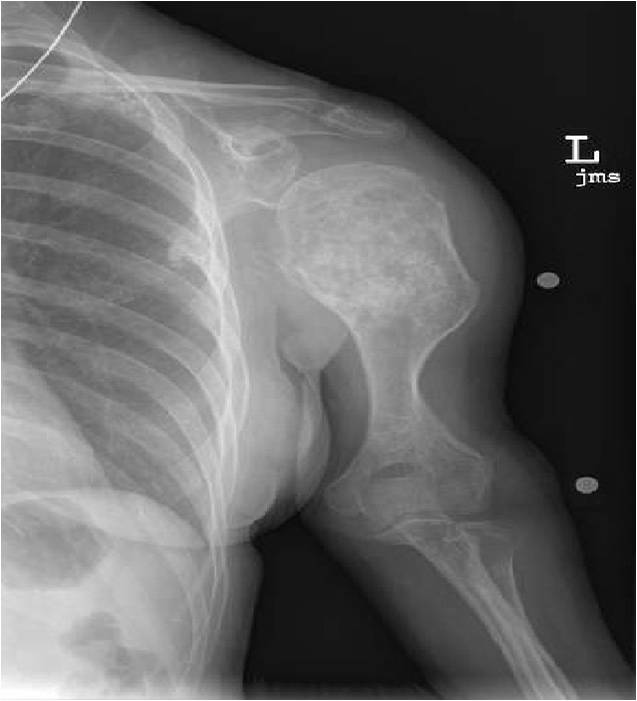

- Proximal Humerus, Femur most common long bones

- Localized, radiolucent defect usually with punctate calcifications

- Calcifications are stippled, punctate, popcorn like calcifications and “Ring and Arc” calcifications

- Geographic lytic lesion

- Expansile remodeling with thinned cortex

- Chondroid matrix with calcifications in majority of tumors

- There should never be any cortical destruction nor a soft tissue component. If this exists then the tumor must be a chondrosarcoma.

- Endosteal scalloping and cortical expansion is acceptable for phalangeal tumors. In most benign long bone cartilage tumors there is minimal endosteal scalloping but there should be no cortical expansion nor thickening. There should be no cortical destruction and no soft tissue component associated with an enchondroma. Cortical destruction, periosteal thickening, cortical expansion and a soft tissue component indicates a chondrosarcoma of the long bone.